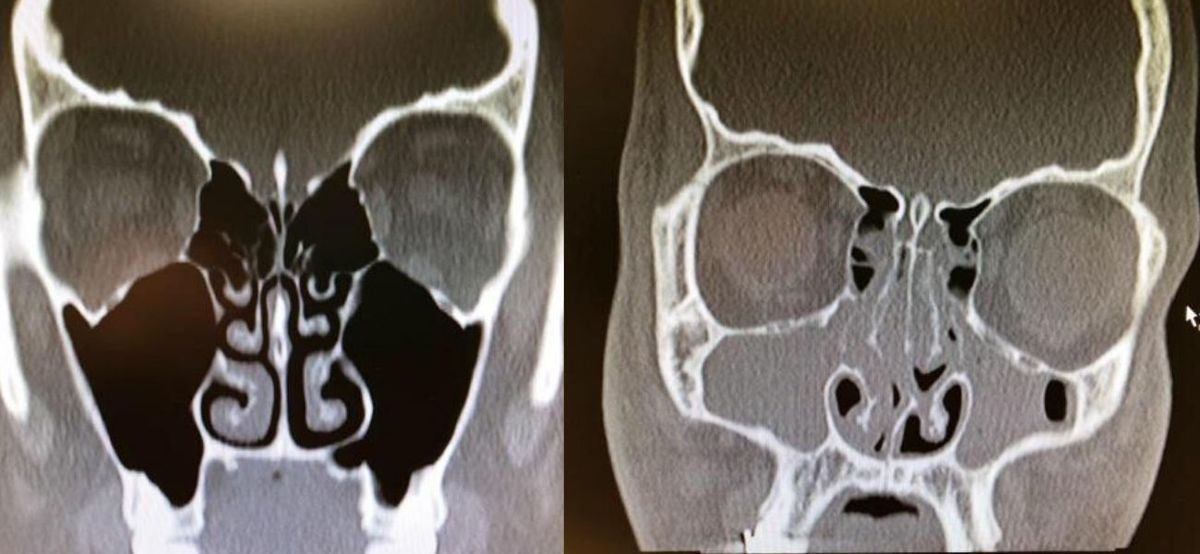

Xrays Of Congested And Un-congested Sinuses Will Make You Grateful For Air

This is really wild. This person had bad congestion and allergies so their sinuses were completely swelled up.

If this doesn't make you breathe a little easier then I don't know what will because I am feeling thankful for my un-congested sinuses right now.